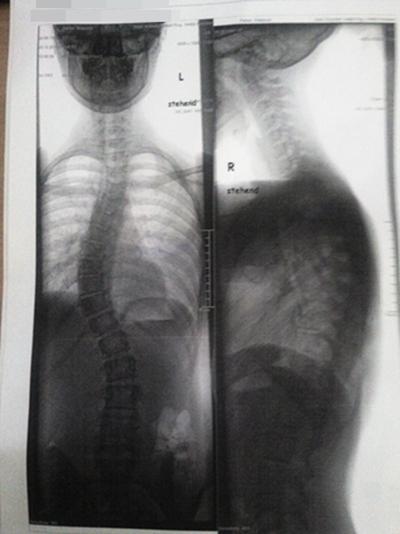

Ich war heute wieder bei meiner Physiotherapeutin, und ich habe jetzt mein erstes Röntgenbild wieder.

(Im Anhang).. Und September muss ich wieder zu meiner achsotollen Orthopädin,die will sich nur mal meinen Rücken ansehen. Außerdem wurde nun endlich der Antrag für die ReHa abgeschickt! :)

Mein erstes RöBi.

gh.JPG (23.63 KiB) 9333 mal betrachtet

ich hab mal die zwei Röntgenbilder (vorher und im Korsett) nebeneinander gelegt. Auch wenn das Größenverhältnis nicht exakt 1:1 ist (sorry dafür, aber ich hab's auf die Schnelle gemacht), kann man glaub ich gut erkennen, dass dein Korsett dich viel zu wenig korrigiert. Ich kann dir auch nur nochmal dringend raten, schnellstmöglich Herr Nahr zu kontaktieren!!! Aber schau mal selbst die Bilder im Vergleich :nein:

So nebeneinander betrachtet ist die Korsett-Korrektur sehr minimalistisch.